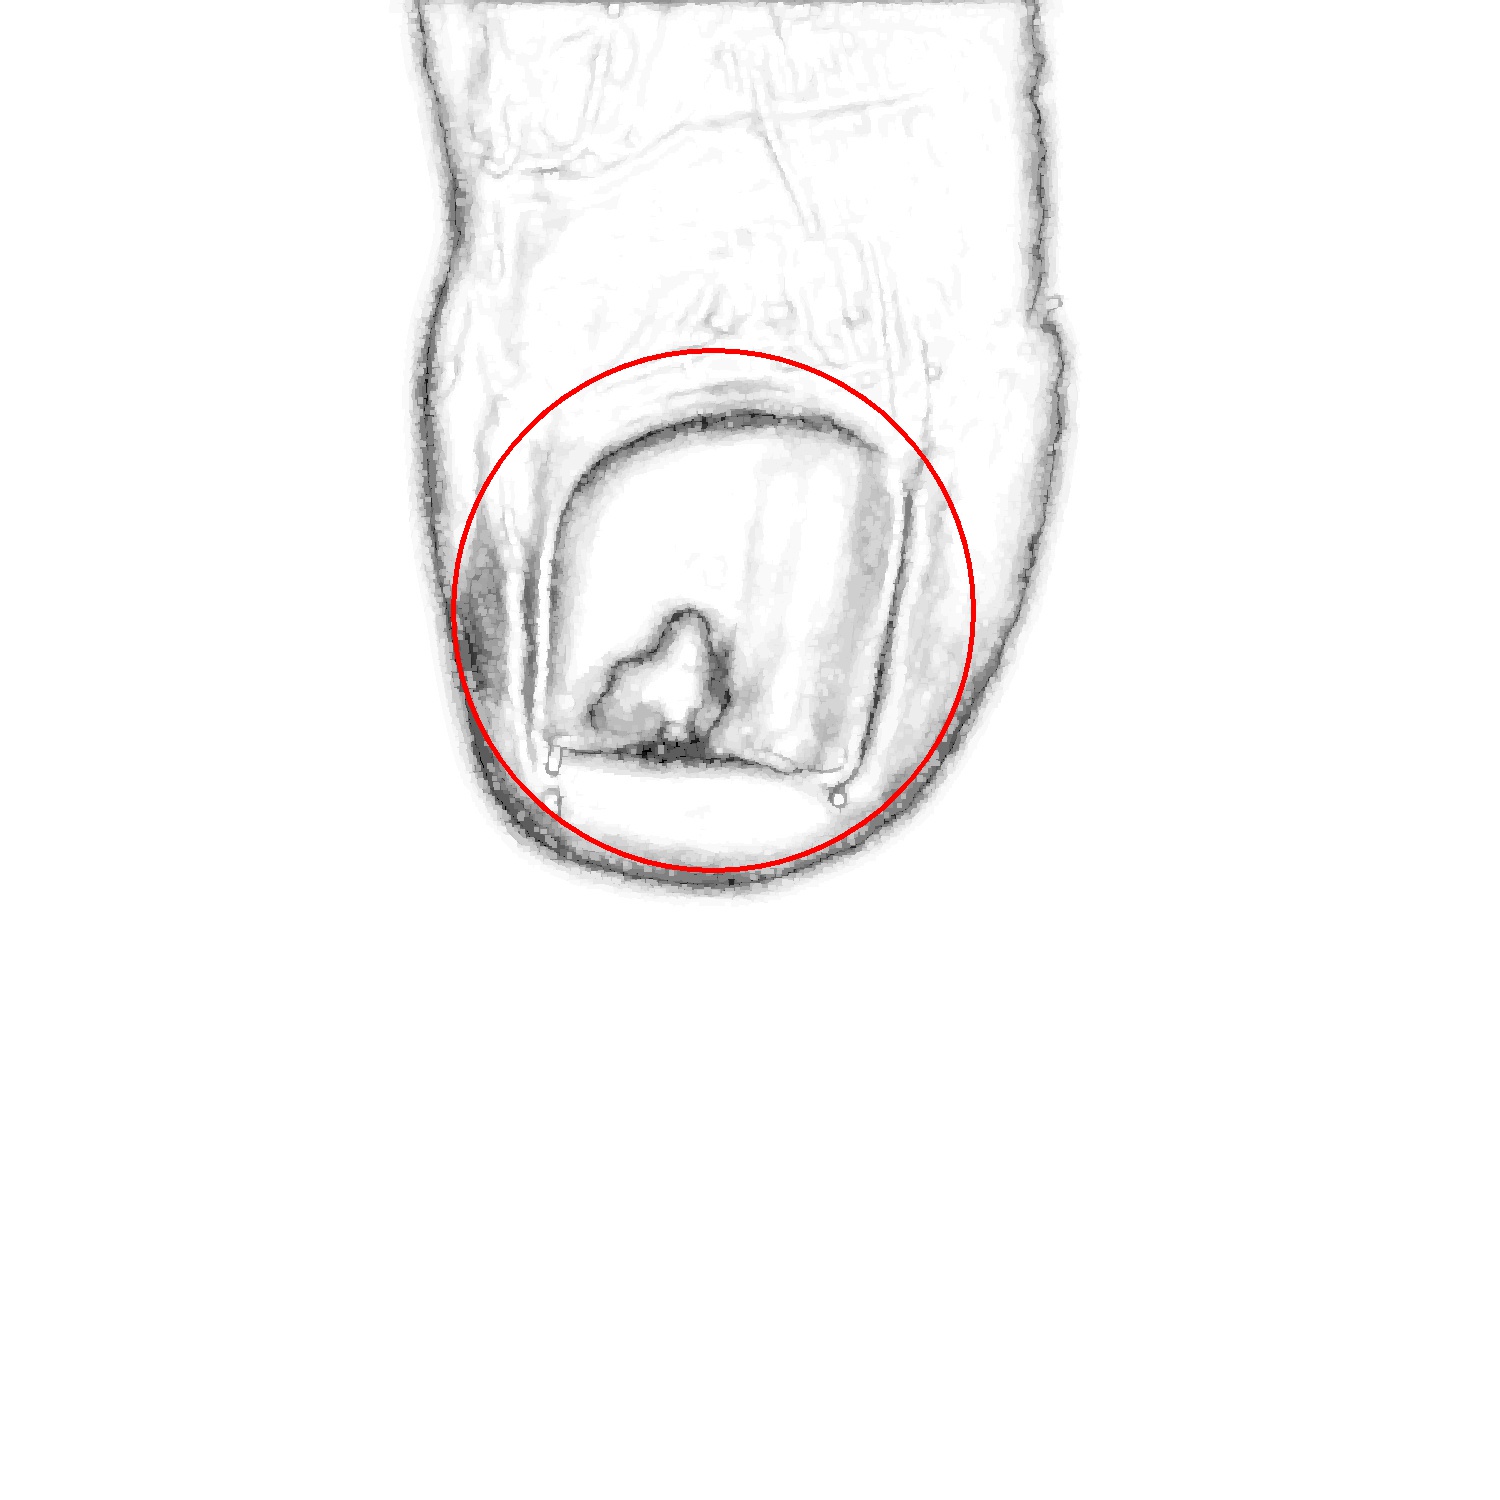

Before tackling the image segmentation problem, we perform an image normalization process based on the template’s known measures. It consists on transforming the input image, as seen in Fig. 3 (left), to an image with standard dimensions and orientation, Fig. 3 (right). To achieve our objective we detect the position of the template corners and geometrically transform the image with an affine mapping. As a result, all normalized images appear to had been taken under the same point of view. We remark that the three template colored squares are mapped to the top-right, bottom-right and bottom-left image corners. In particular, left foot images are mirrored. Normalized images are always set to measure pixels. Since the real region inside the template measures cm, a centimetre in the normalized image accounts for 300 pixels, which can be used to measure distances and areas.

In the following, we describe each step taken to deal with the task of segmenting the toenail from images like the one in Fig. 3 (right). In particular, Fig. 4 contains a flow diagram, along with the algorithm employed for each of them.

In order to select the tip of the toe, we segment the foot regions from the background template. Then, the Hough transform is used to detect a circle in the foot region, which corresponds to the tip of the toe. Next, the nail is found within the tip of the toe using a second Hough transform, that depends on the result of the first one. Specifically, this second Hough transform is computed taking into account only the edges that are in the tip of the toe circular estimation. In the following, we detail the transformations performed.

Finally, we detect the circle that better fits the nail using a second Hough transform. We discard the edges far from the tip of the toe circle (see Fig. 5(c)), so that we mainly keep the nail edges. Thus, this second Hough transform is prone to detect the circle that best fits the nail. Also, we constrain the radius of this circle according to the size of the tip of the toe. Specifically, we expect the nail radius to be smaller than the radius of the tip of the toe circle (see Fig. 5(b)) but bigger than half of its measure. The most prominent circle (see Fig. 5(d)) is the one selected as nail circle. Experimentally, the results of this process have proved to always find a location on the nail (the circle center) and a good estimation of the nail size (derived from the radius).